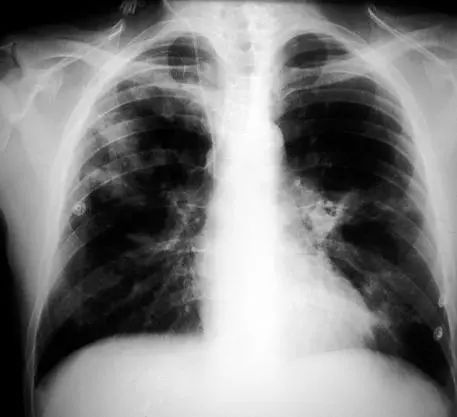

图1.2 细菌性肺炎。双肺下叶肺炎患者影像。